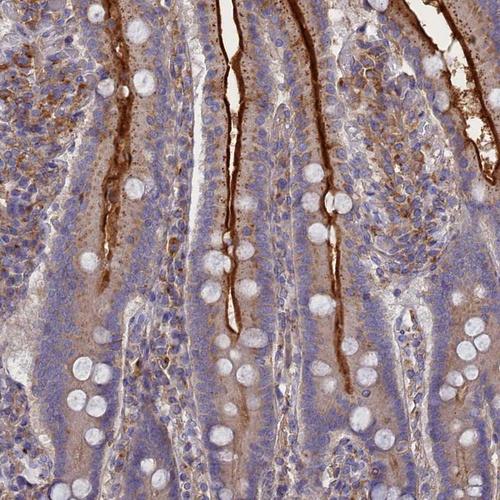

Immunohistochemical staining of human fallopian tube shows strong cytoplasmic positivity in glandular cells.